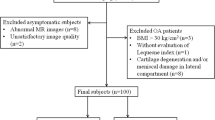

The National Medical Ethics Committee approved the study and written informed consent was obtained from all participants. Twelve matched pairs (12 healthy volunteers and 12 patients with prior anterior cruciate ligament repair) were recruited for the study.

A total of 247 patients underwent anterior cruciate ligament repair (ACLR) at the Orthopaedic Department at our institution in the years 2008 and 2009. The inclusion criteria for the ACLR group were (1) 16–45 years at time of ACLR, (2) transtibial ACLR technique performed by a single senior surgeon using the same graft fixation, (3) quadruple stranded semitendinosus-gracilis tendon graft, (4) intact lateral meniscus at ACLR according to arthroscopy records (5) body mass index (BMI) of 18.5 to 30, (6) preoperative sports activity of at least 4 on the Tegner scale. All ACLR procedures were performed by a senior orthopedic surgeon (O.Z.); in the tibial tunnel graft was fixed with Milagro interference screw (DePuyMitek, Raynham, MA, USA) and in the femoral tunnel graft was fixed with RIGIDfix (Mitek, Johnson & Johnson, Norwood, MA, USA) [8]. All patients underwent an identical rehabilitation program. Based on the arthroscopy record and patient’s history, the following exclusion criteria were established (1) known chondropathy, (2) concomitant collateral ligament injury, (3) concomitant posterior cruciate ligament injury, (4) MR contraindication, and (5) meniscal tear at ACLR. Twenty-three patients met the study inclusion criteria, however only 15 were successfully contacted. In three patients, graft rupture was identified on MR examination, and thus were excluded from the study. Thus, 12 patients (nine male, three female) were included in the study (Table 1). The average time from the ACLR to the MR examination was 6.3 ± 0.5 years.

Twelve healthy volunteers were recruited to a control group, with each participant matched to an ACLR patient according to age and sex. The inclusion criteria for the control group were (1) International Knee Documentation Committee Subjective Knee Form (IKDC) score of at least 95 and (2) no history indicative of any knee joint disorder.